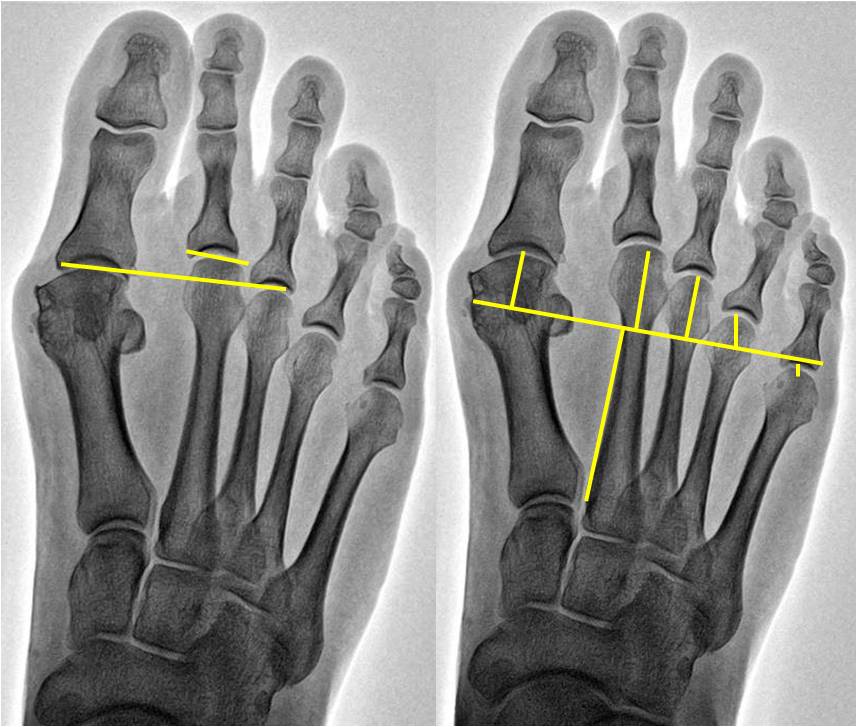

While the metatarsal parabola is an important part of plantar plate repair, there is not a strong understanding of what constitutes an “optimal” parabola. Sansone described the metatarsal parabola as a source of forefoot imbalance and possible source of pain.1 Over time, many authors have tried to describe the “harmonious” parabola or the “correct parabola.”2-4 This has resulted in multiple ways of measuring the metatarsal parabola and more recently, authors have questioned the reliability of measurement of these structures.5,6

Waverly and coworkers addressed this topic in a study presented at the American College of Foot and Ankle Surgeons (ACFAS) Annual Scientific Conference this past year.17 One hundred total feet were included in this study. In order to be included, patients had to have had surgery on the second metatarsophalangeal joint (MPJ) on one foot by a surgeon from our practice and had no surgery on the contralateral foot. Patients had pressure analysis on both feet and bilateral weightbearing radiographs. The radiographic analysis focused on evaluation of the metatarsal parabola by four different methods. Researchers then correlated this to the pressure analysis data and performed multiple linear regression analyses.

Fleischer and colleagues published a second study in 2017 that was a case control-matched trial.7 There were 300 total patients and two controls for each case. The authors defined a case as involving a patient who had a non-acute, isolated second MPJ pain with intraoperative confirmation of a plantar plate injury. Controls were patients who had pain outside the forefoot but were matched in age, gender and year of presentation. The authors reviewed medical records for demographic information, body mass index and smoking status. Researchers reviewed radiographs for forefoot angles and metatarsal parabola measurements.

The study authors found that the only variable that had an association with plantar plate pathology on the univariate and multivariate analysis was a metatarsal protrusion distance of greater than 4 mm.7 Patients with a second metatarsal length greater than 4 mm had a nearly 2.5 times greater chance of plantar plate injuries. Furthermore, an elongated second metatarsal exhibited a positive dose–response relationship. Patients with increasingly longer second metatarsals were more likely to present with plantar plate injuries.